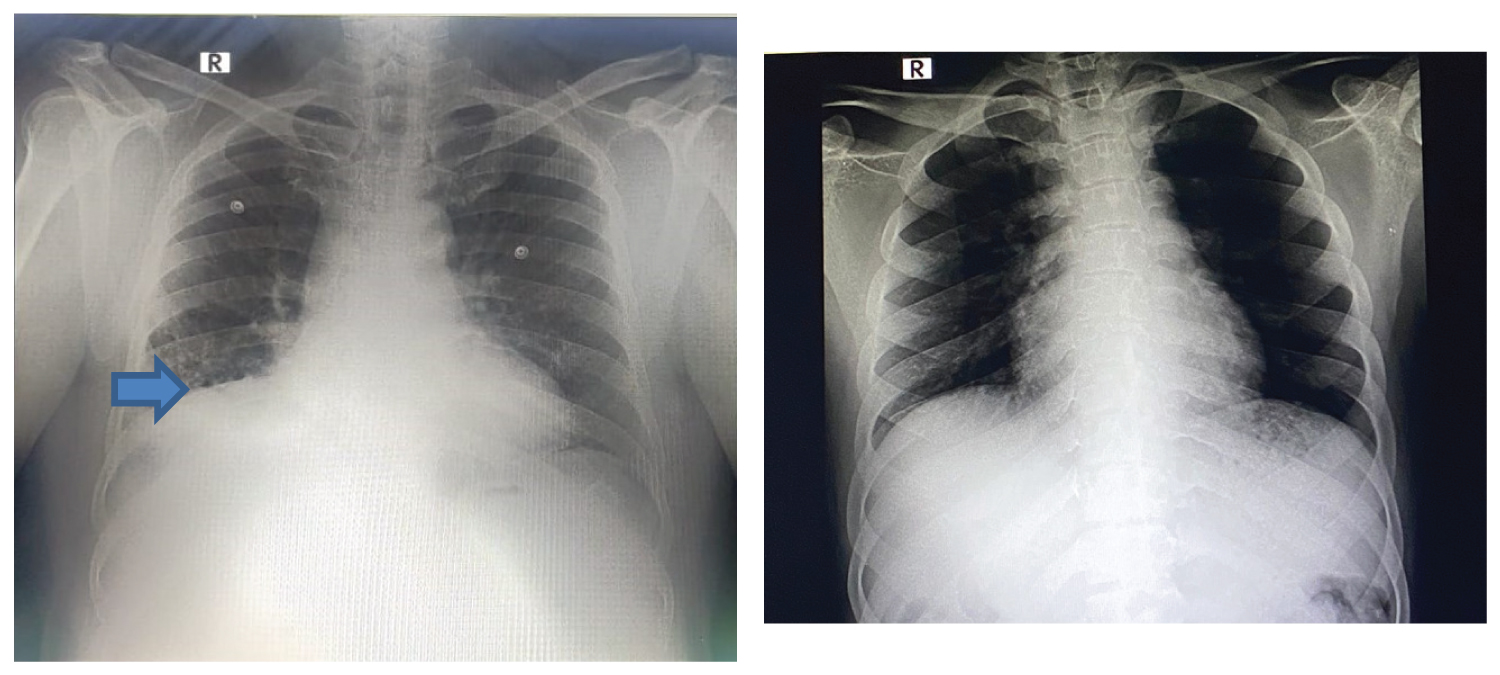

A 66-year-old male, diabetic and hypertensive presenting with fever and cough for a week was diagnosed to have right endobronchial growth (Figure 1) and post obstructive pneumonia in right lower lobe, confirmed with Chest X-ray (Figure 2), Computed Tomography (CT) Thorax and flexible bronchoscopy (Biopsy - squamous metaplasia). Pre-operative optimization included a course of antibiotics and bronchodilator therapy. Consent included explanation of risks of airway bleeding, trauma, perioperative airway oedema and remote chances of postoperative ventilation. Sedation the day before surgery was avoided. Standard monitoring was done. Well-functioning suction apparatus, Double lumen tube (DLT) and bronchial blocker were kept standby for lung isolation in case of massive airway bleeding. Maximum allowable neck extension was checked prior to induction with shoulder roll and head ring. Patient was preoxygenated with 100% Fraction of Inspired Oxygen FiO 2 , premedicated with glycopyrrolate 10 µg/kg, ondansetron 0.15 mg/kg, fentanyl 2 µg/kg and induced with propofol 2 mg/kg and paralyzed with atracurium 0.5 mg/kg. 11 mm rigid bronchoscope was passed after positioning with neck extension by pulmonologist. Ventilation was done via side port with intermittent apnoeic periods. Arterial line was secured and transduced. Anaesthesia was maintained with propofol infusion 10-15 mg/kg/hr throughout the case, depth of anaesthesia monitored by Bispectral Index (BIS) adjusted to 40-60. Analgesia was provided with repeated doses of fentanyl 0.5 µg/kg at half hourly intervals and IV paracetamol 1g. FiO 2 was kept at 0.5 and reduced to 0.3 at the times of cautery use to prevent airway burns. Higher flows of 5 to 6 litres/minute were used throughout the case. Atracurium boluses of 10 mg was given every 30 minutes. Blunting of sympathetic responses was done with esmolol infusion, bolus of 500 µg/kg over 10 minutes followed by infusion of 50-100 µg/kg/min. Steroids in the form of intravenous hydrocortisone 100 mg and dexamethasone 8 mg was given to prevent airway oedema. Endobronchial mass was detached using electrocautery and extraction was done piecemeal using cryoprobe as it was difficult to remove en masse. Minimal bleeding was noted, managed by suctioning. Final check scopy showed patency of all bronchi. Thorough suctioning and xylocard 1 mg/kg sprayed into the airway at the end of procedure. After removal of bronchoscope intubation with size 8.0 mm endotracheal tube was done and ventilated for about 15 minutes. Arterial Blood Gas (ABG) done following the procedure was normal. Patient was extubated uneventfully and was monitored in Intensive Care Unit (ICU) for 24 hours. We did not encounter any significant postoperative complications.

Figure 2: Chest X-ray before and after debulking of tumor. Blue arrow indicates the non-homogenous opacity in the right lower zone (case 1). View Figure 2